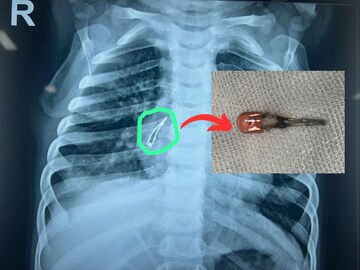

Ahmedabad: A similar case for parents has come up. A nine -month -old baby’s toy’s mobile LED bulb swallowed the bulb in the breathing tube. The pediatric surgeons at Ahmedabad Civil Hospital performed a successful surgery. Parents and families need to be more careful about the frequent occurrence of such cases.

The 9-month-old son of a resident of Junagadh, Mangrol, Junagadh, has been coughing for the last 15 days. Showing a pediatrician in Junagadh, his chest was found to have something in the respiratory tract. Further investigation was recommended by the private hospital in Rajkot but he could not afford it, and he brought the child for treatment at a civil hospital in Ahmedabad.

Head of Pediatric Surgery Department of Civil Hospital, Ahmedabad. Rakesh Joshi and Professor of Anesthesia Department Dr. An LED bulb was successfully evacuated from the main bronchial of the right side by Nilesh and his team. After the operation, the health of the child is improving rapidly and without any other problems the baby is now healthy so he will be discharged from the hospital soon, doctors said.